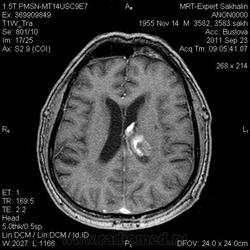

ID:53258

Онмк по геморрагичесому типу с образованием внутримозговой гематомы (подострая аза), прорывом в полость левого бокового и III -го желудочков.

Да, спасибо.Мы так же расценили.

по дате онмк - острая фаза.

Цель введения контраста наверное для исключения объема. Хотя. Наверное только динамика ответить на данный момент. Надо выносить в заключение весь диагностической ряд. Но больше похоже действительно на зона геморрагического НК. А сосуды не делали? Может имеет место венозное нарушение?

И почему острая фаза?Подострый период.

Да, подострый, не знаю куда я смотрел, что насчитал менее 3 дней.